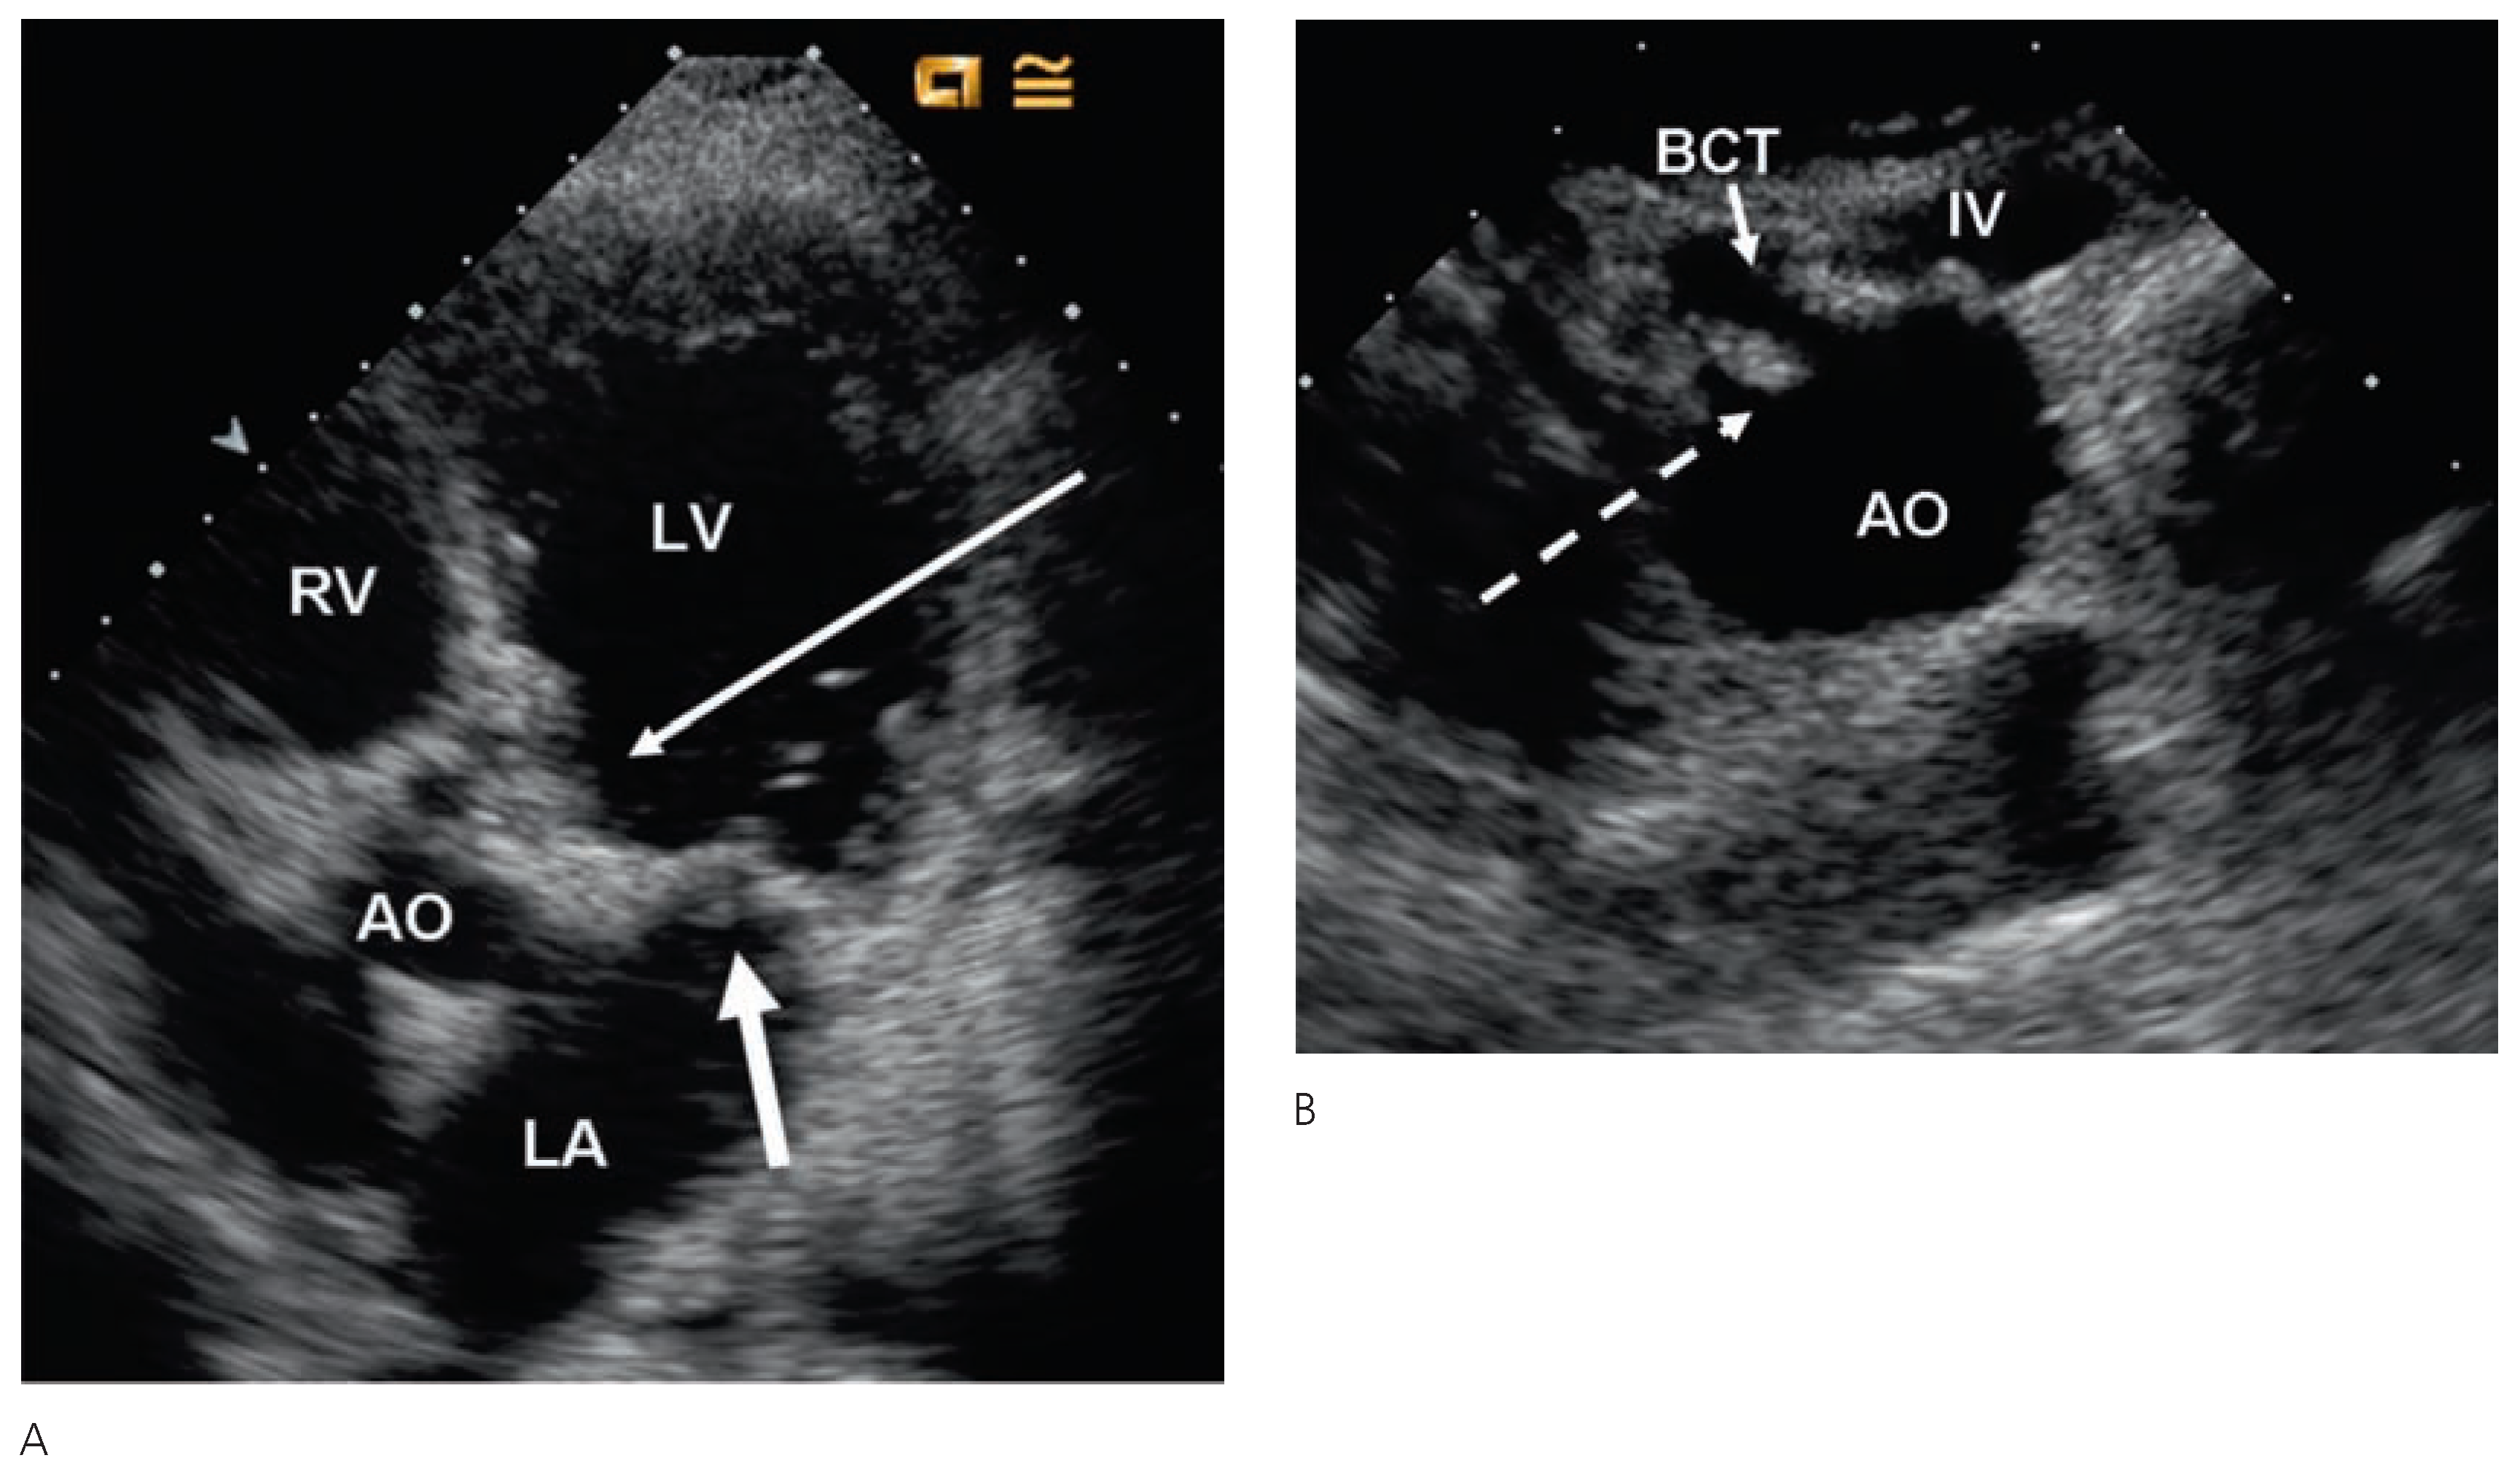

Echocardiographic findings

|

Valvular heart disease

Coronary artery disease after radiation therapy